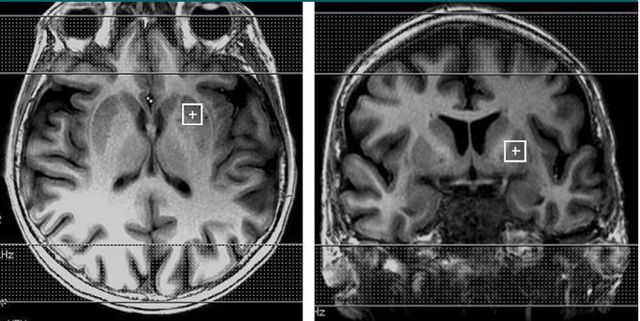

在本研究中,研究对象分为三个组:用左旋多巴治疗的帕金森病患者,停用左旋多巴药物的帕金森病患者,和正常志愿者。MRI 检查采用的序列为短回波(29msec)氢质子磁共振波谱成像(MRS),单体素(1 cm3)进行扫描,感兴趣区放置在双侧壳核,如图 1.

图 1. MRS 序列单体素扫描感兴趣区放置的位置